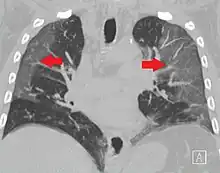

CT showing diffuse ground-glass opacities in periphery of both lungs in patient with COVID-19.

Ground-glass opacity is among the most common imaging findings in patients with confirmed COVID-19.[16][17] One systematic review found that among patients with COVID-19 and abnormal lung findings on CT, greater than 80% had GGOs, with greater than 50% having mixed GGOs and consolidation.[16] GGOs with mixed consolidation has most often been found in elderly populations.[18] Several studies have described a pattern among initial, intermediate, and hospital discharge imaging findings in the disease course of COVID-19. Most commonly, initial CT imaging reveals bilateral GGOs at the periphery of the lungs. During initial stages, this is most often found in the lower lobes, although involvement of the upper lobes and right middle lobe has also been reported early in the disease course.[16][18] This is in contrast to the two similar coronaviruses, SARS and MERS, which more commonly involve only one lung on initial imaging.[19][20] As the COVID-19 infection progresses, GGOs typically become more diffuse and often progress to consolidation.[11][18] This is sometimes accompanied by the development of a crazy paving pattern and interlobular septal thickening.[18] In many cases the most severe pulmonary CT abnormalities occurred within 2 weeks after symptoms began.[17] At this point, many individuals begin showing resolution of consolidation and GGOs as symptoms improve. However, some patients have worsening symptoms and imaging findings, with further increase in septal thickening, GGOs, and consolidation. These patients may develop lung "white-out" with progression to acute respiratory distress syndrome (ARDS) requiring treatment escalation.[17][21]

Preliminary reports have shown many patients have residual GGOs at time of discharge from the hospital. Due to the novelty of COVID-19, large studies investigating the long-term pulmonary CT changes have yet to be completed. However, long-term pulmonary changes have been seen in patients after recovery from SARS and MERS, suggesting the possibility of similar long-term complications in patients who have recovered from acute COVID-19 infection.[22]